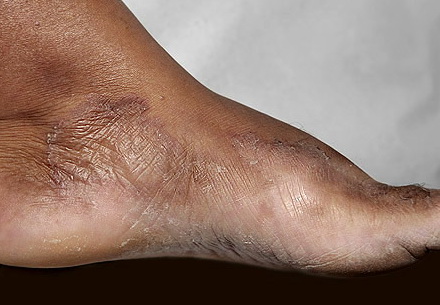

Chronic Hyperkeratotic Type.

Usually bilateral with patchy or diffuse scaling limited to the thick skin, soles, and the lateral and medial aspects of the feet, this is also known as “moccasin-type” tinea pedis. T. rubrum, the most common etiology, produces very few minute vesicles, leaving collarettes of scale less than 2 mm in diameter. Erythema is variable.